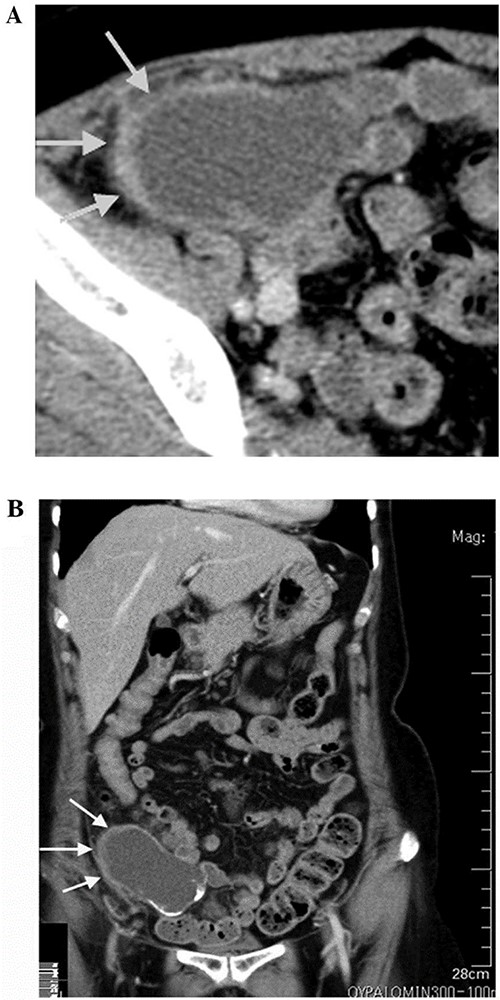

Computed tomography (CT) scan was performed after perfusion of a radiopaque substance through the vein in both arterial and venous phases. It exhibited a 14-cm lobulated cystic formation in the level of the right iliac vessels with an extension to the upper margin of the pelvis. The wall of the cyst was thick and calcinated (Fig. 1).

CT scan showing lobulated cystic formation in the right iliac vessels level with an extension to the upper margin of the pelvis. This finding is suspicious, so a decison was made for excision of the tumor and to be sent to pathology department to confirm the diagnosis.

Often, this malignancy is misdiagnosed as acute appendicitis, retroperitoneal tumors in the right iliac fossa or an adnexal mass. Imaging tools used for diagnosis are ultrasound and CT. CT findings include cystic dilation within the appendiceal lumen with wall calcifications and irregular appendiceal wall thickening as demonstrated in our case. Grossly, specimens include hyalinization and fibrosis of the appendiceal wall with a grossly swollen appendix secondary to mucinous accumulation [4].